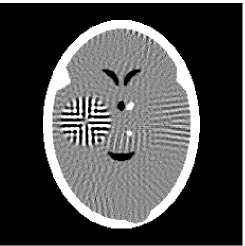

Furthermore, we used the classic ART iteration as the iteration operator in our numerical experiments. In order to compare the proposed superiorization algorithm with the classic superiorization algorithm, we applied the classic superiorization and -PP superiorization algorithm to two phantoms (see figure 1). The first one is the Shepp-Logan phantom[30], and the second one is the head phantom with a ghost which is invisible at 22 specified projection directions [10, 31]. In addition, we compare the performances of the two algorithms for the noiseless and noised data with different projections. In all experiments, the noised projection data was corrupted by additive Gaussian white noise with variance . We record the iterations, running time of program and mean square error (MSE) of different algorithms, where MSE is computed by

3.2 Ghost phantom

Noiseless projection data: Since the ghost in this phantom is invisible at 22 directions [10, 11], the reconstruction images usually suffer from artifacts. in our simulations, the projection data were collected in 112 and 82 directions: 90 and 60 with equal angle increments from to and 22 specified views in which the ghost is invisible [10]. Iteration procedures were terminated when for the noiseless projections.

The reconstruction images from the noiseless projection data were shown in the Fig. 6. For comparison, Table 3 present the iterations, MSE, Res and running time(RT) of different reconstruction results.